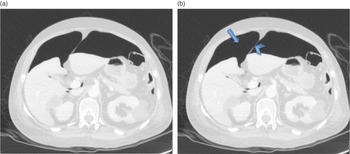

Dynamic Radiology of the Abdomen: Normal and Pathologic,

Dynamic Radiology of the Abdomen: Normal and Pathologic, Radiologia Dinâmica do Abdome | Amazon.com.br,

Radiologia Dinâmica do Abdome | Amazon.com.br, Meyers' Dynamic Radiology of the Abdomen: Normal and,

Meyers' Dynamic Radiology of the Abdomen: Normal and, Meyers' Dynamic Radiology of the Abdomen: Normal and,

Meyers' Dynamic Radiology of the Abdomen: Normal and, Imaging of the Abdomen (2.10) - Intensive Care Medicine

Imaging of the Abdomen (2.10) - Intensive Care Medicine『Novak's Textbook of Gynecology 医学書 洋書』